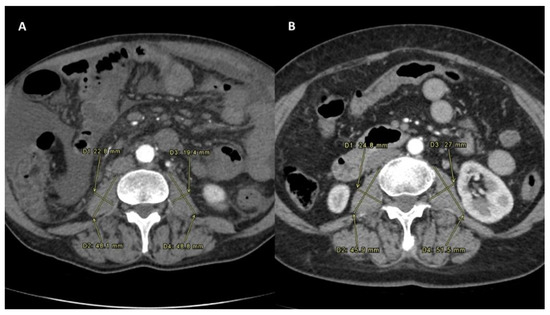

At the radiological response evaluation of the tumor according to the mRECIST criteria, the two groups were similar in terms of rates of complete response (p = 0.42), partial response (p = 0.26) and stable disease (p = 0.59). Only the progressive disease (PD) was more commonly observed in the Sarcopenia group (38.6% vs. 11.9%; p = 0.006). When both intra- and extra-hepatic PD was evaluated, also in this case, a greater percentage of cases was observed in the Sarcopenia group (45.5% vs. 16.7%; p = 0.005). Dose distribution and m-RECIST response were evaluated through SPECT/CT scan and multiphasic CT, as shown in Figure 4.

Figure 4. Upper row (AC) shows patient who underwent to progression disease. Lower row (DF) shows patient who underwent to complete response. (A,D) show liver disease on multiphasic CT before intra-arterial radioembolization. (B,E) show correctly targeted radioembolization on post-procedural SPECT–CT. (C,F) show tumor response on CT follow up.